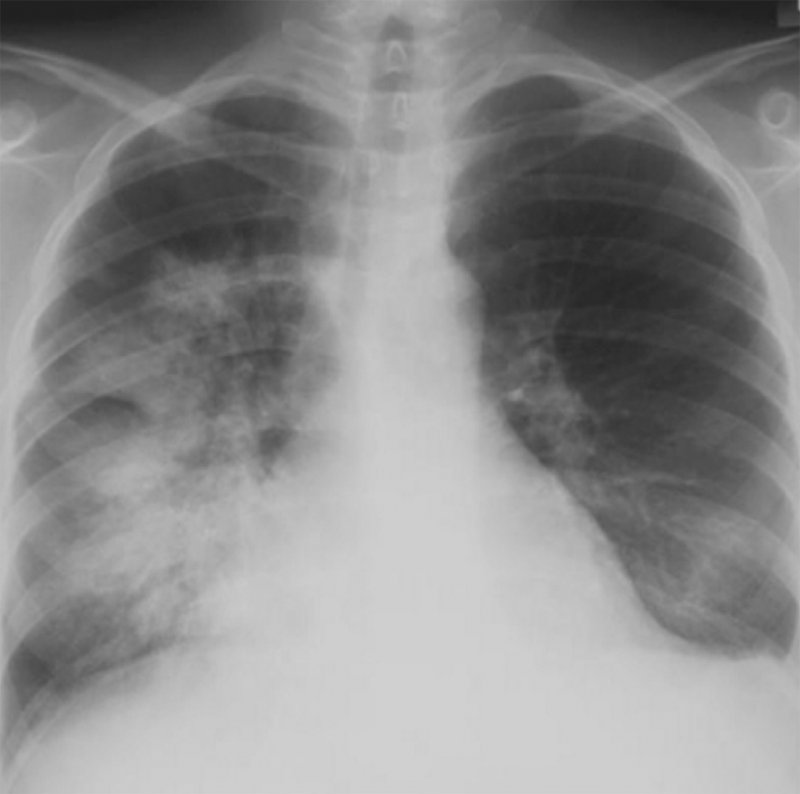

Волчаночный пневмонит (люпус-пневмонит) характеризуется одно- или двусторонними участками интерстициальной инфильтрации по типу «матового стекла», которые могут сочетаться с альвеолярной инфильтрацией. Эта патология встречается гораздо реже. Отметим, что при системной красной волчанке может возникать легочное кровотечение, при этом на рентгенограмме легких определяются распространенные инфильтраты (рисунок 1). Кроме этого, при системной красной волчанке в нижних отделах легких могут обнаруживаться фиброзные изменения, однако выраженный фиброз и «сотовое легкое» развиваются редко.

Рисунок 1. Поражение легких при системной красной волчанке. На рентгенограмме, выполненной у больного с кровохарканьем, обусловленного обширным легочным кровотечением, в прикорневой зоне и среднем легочном поле справа определяется высокоинтенсивная, нечетко ограниченная инфильтрация, также в нижней доле слева визуализируется начальная инфильтрация. Слева отмечается небольшой плевральный выпот